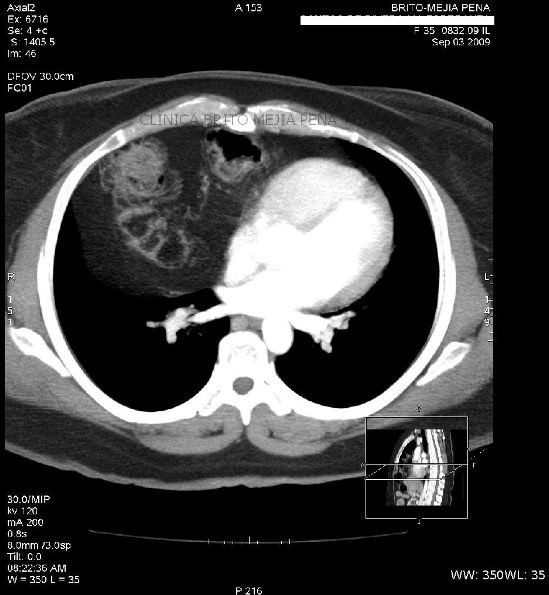

Aneurisma Aorta Ascendente